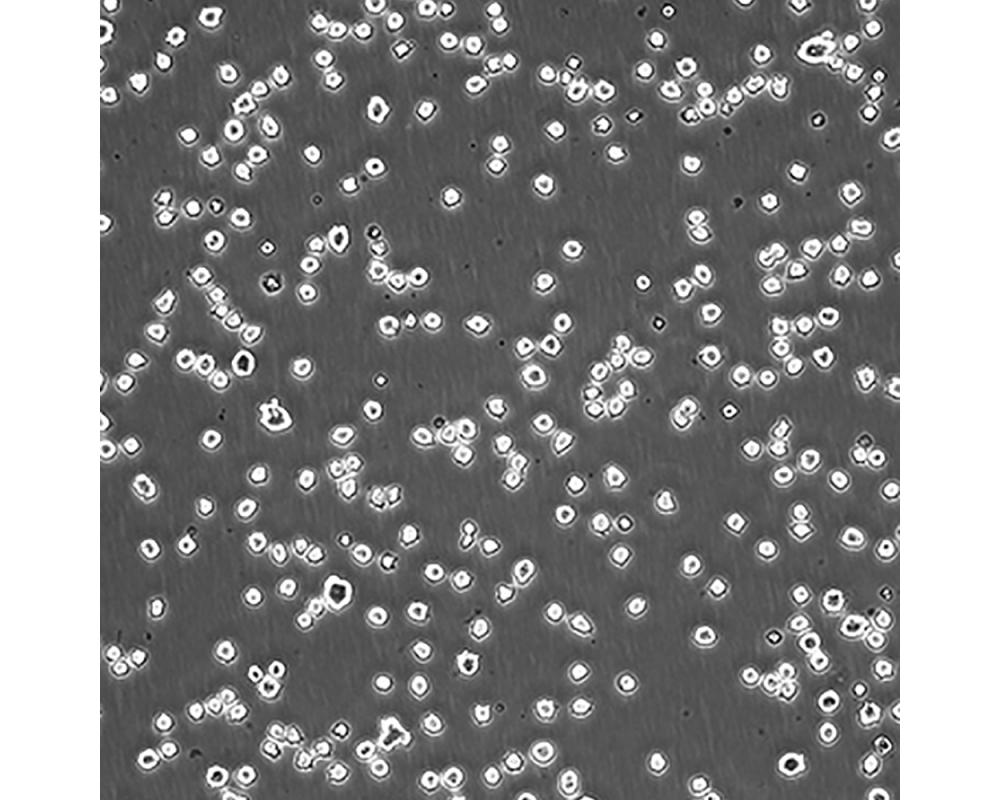

產品名稱 DB

中文名稱 人彌漫性大B細胞淋巴瘤細胞

組織來源 彌漫性大B細胞淋巴瘤;男性

生長特性 懸浮